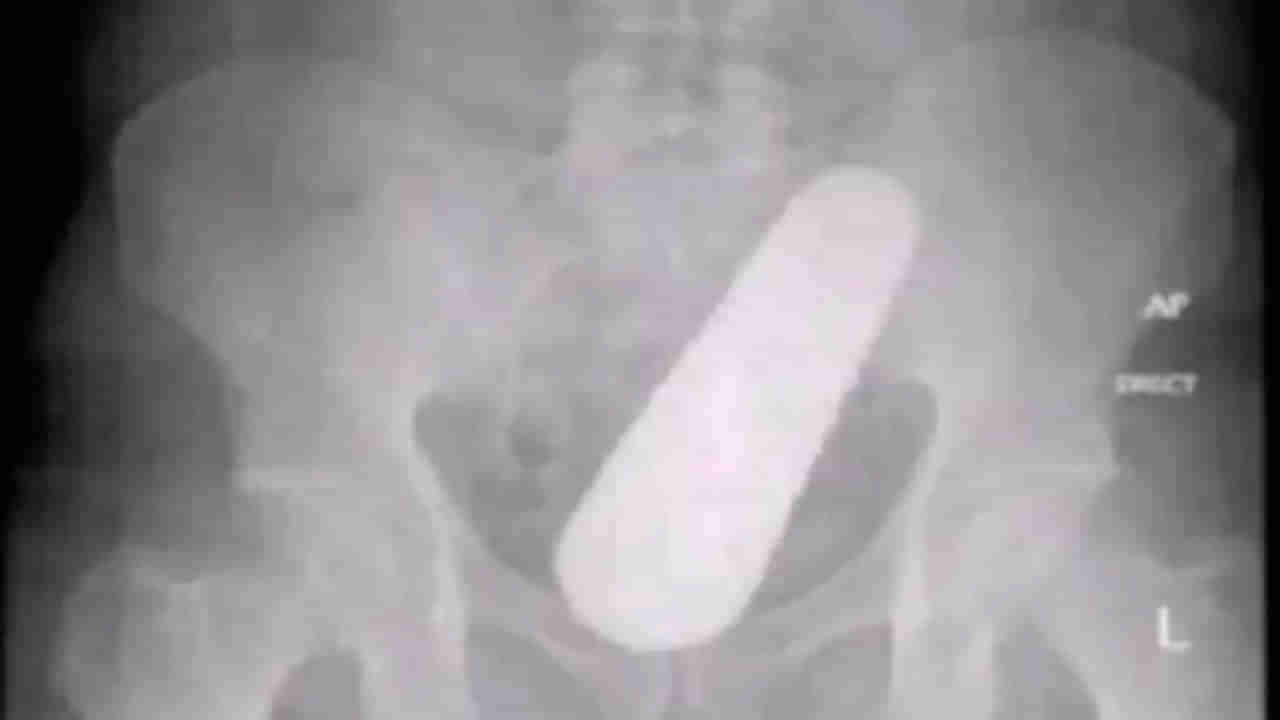

వివరాల్లోకి వెళ్తే.. కొలంబియాలోని బారానోయికు చెందిన 40 ఏళ్ల వ్యక్తి తన ప్రైవేటు పార్టులో తీవ్రమైన నొప్పితో నడవలేక.. చివరికి హాస్పిటల్కు వచ్చాడు. అక్కడున్న డాక్టర్లు అతడికి పలు పరీక్షలు నిర్వహించి.. ఎక్స్రే తీశారు. ఇక వారికి అందులో కనిపించిన వస్తువు చూసి దెబ్బకు షాకయ్యారు. వెంటనే ఆపరేషన్ చేసి దాన్ని బయటికి తీయడంతో.. అది సొరకాయ అని గుర్తించారు. మల ద్వారం నుంచి ఆ సొరకాయ లోపలికి వెళ్లిందని డాక్టర్లు నిర్ధారించుకున్నారు. అంతా సజావుగా జరగడంతో ఆపరేషన్ అనంతరం.. పేషెంట్ను సొరకాయ ఎలా బాడీలోకి వెళ్లిందని అడగ్గా.. తాను ఎక్కువగా సొరకాయలు తింటుంటానని.. వాటి గింజల ద్వారా తన కడుపులో సొరకాయ పెరిగిందని చెప్పాడు. కానీ అతడు చెప్పిన మాటలను నమ్మని వైద్యులు.. చివరికి పేషెంట్ను ఇంటికి పంపించారు.(Source)